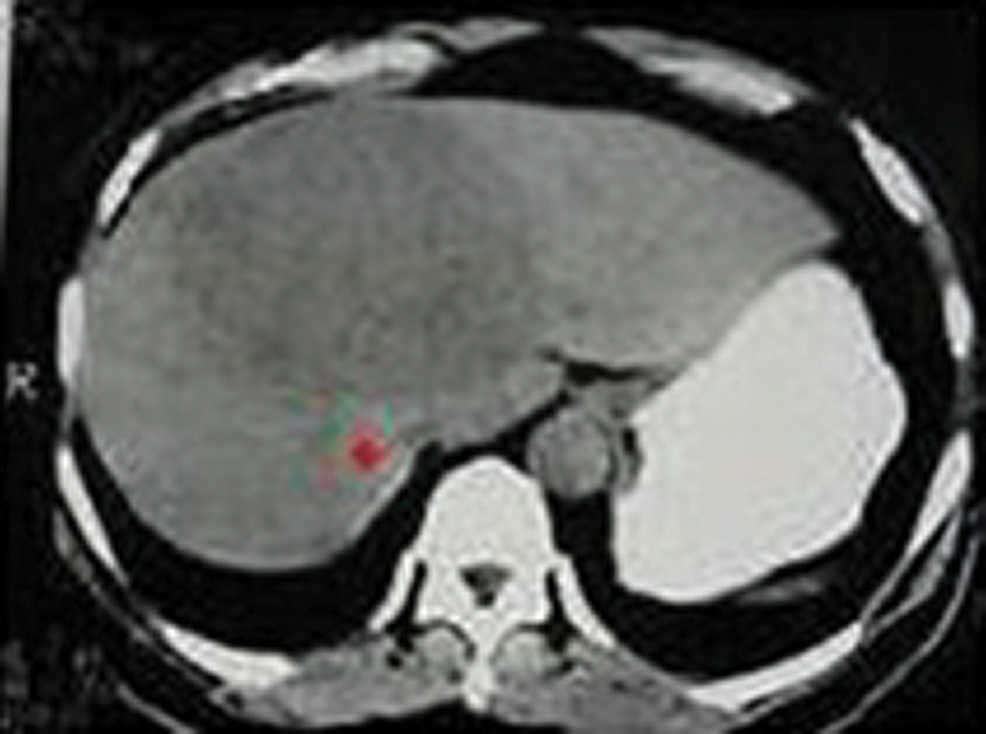

A sample input CT image is shown in Fig. 2. It is processed using guided filter to smoothen the boundaries to facilitate more accurate level set segmentation. The processed CT image shown in Fig. 4 is now used for level set segmentation where segmented liver region is obtained.

Figure 2: Abdominal CT input image

Figure 3: Seed point selection using the proposed algorithm

The above Fig. 3 shows the image with seed point selection marked in it and Fig. 5 shows the growing contour which covers the liver image.